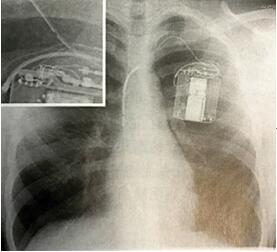

与成人相比,电极故障在儿童人群具有更高的发生率(图2),一些报道可达21%。电极故障的发生率在年轻、体型小的患儿中最高,并且与身高增长相关。直径较小的电极特别受儿科欢迎,但与其他电极相比,其植入失败率更高,认为和需要减小直径的特殊设计有关。Sprint Fidelis是一种特殊的电极,2007年因电极断裂发生率较高而被召回,其应用于儿童和青少年的年故障率为9.1%,而其他电极仅为2.3%。在这项研究中,139例(14%)患儿出现电极故障,电极平均寿命为(2.0±1.4)年,由此导致53例患儿发生不恰当治疗。发生电极故障时通常需要取出电极,这一过程比较困难,有出血、心肌损伤等风险,并可能需要紧急手术。儿童电极拔除和生存评价研究(PLEASE研究)中共有137例患者实施了电极拔除,出现静脉或心脏创伤等并发症的发生率是4%。

图2 标准及放大胸部X线图像中均可见单腔、双线圈电极ICD的脉冲发生器上电极断裂。该患者因心室电极上的高频噪声接受了多次不恰当治疗